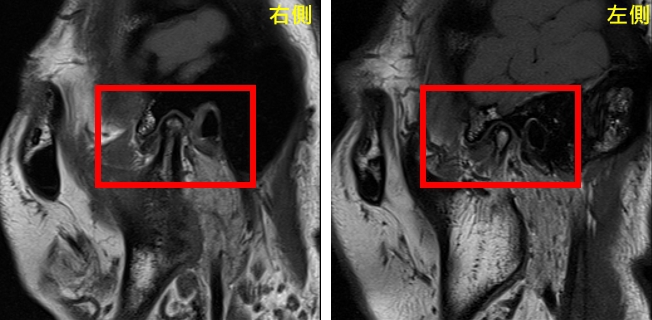

經評估後,由口腔顎面外科呂明怡主治醫師施行關節腔玻尿酸注射,並搭配智慧賦能中心林志峰主任進行震波治療,透過跨專業協作,針對病因進行整體性治療,短短一個月內,曾小姐的顳顎關節疼痛、臉頰緊繃、喉嚨異物感及肩頸痠痛等症狀大幅減輕,隨著持續治療,生活品質顯著提升,也逐漸找回自信與笑容。

中山附醫口腔醫學部部長暨台灣顱顎障礙症學會理事長余權航醫師指出,顳顎關節障礙症候群常伴隨疼痛、咀嚼困難及頭頸部不適等多重症狀,其成因複雜,涉及關節、肌肉、咬合及心理壓力等因素,治療上需仰賴跨領域專業整合。中山附醫智慧賦能中心林志峰主任強調,為提升治療成效,中山附醫率先於國內推動跨領域整合醫療模式,結合口腔醫學、物理治療、影像診斷及心理支持等資源,提供患者全方位照護,未來也將持續深化醫療服務,打造結合臨床、教學與研究的整合平台,陪伴更多患者邁向健康且有品質的生活。